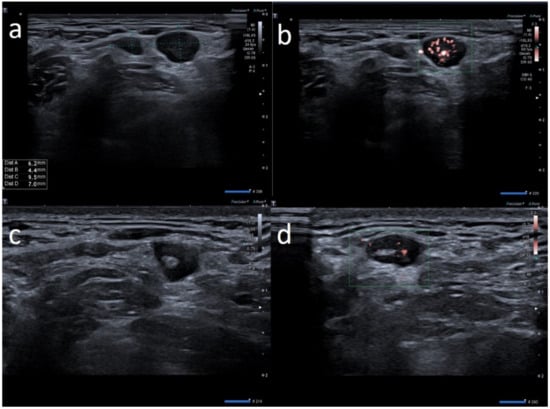

| W | 49 | Pfizer | Axillary ipsilateral to vaccine injection | Occasionally, 6 days after first dose, during breast sonography for oncological surveillance | Breast cancer 3 years ago | 4 | Variable: from 1.0 to 2.0 cm | Ovular | Asimmetric cortical thickening and poor evidence hilum | Stiffness similar to surrounding tissue | Central and peripheral vascular signals | Unnecessary other follow-up |